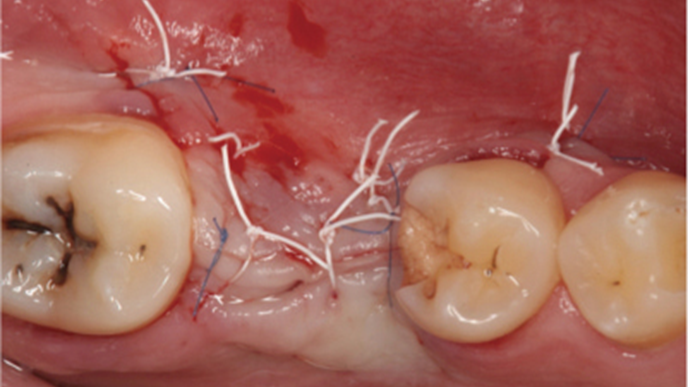

Clinical case: Ridge splitting technique using SmarThor + AnyRidge as expander

- Courtesy of Dr.Kwang-Bum Park, Korea -

AnyRidge, ridge splitting, GBR, Dr. Kwang-Bum Park, mandibular posterior, SmartThor, Mega-Oss, thin ridge, bone regeneration

AnyRidge implant system. SmarThor, Mega-Oss